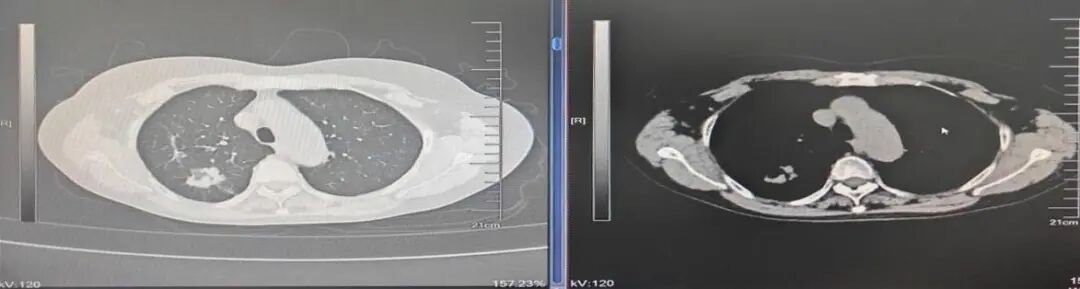

(三)新辅助治疗后的肺癌微创根治术

偏晚期的肺癌手术机会渺茫,新辅助治疗(术前免疫、靶向、化疗等)可让患者重获根治性手术机会。如图:7.7cm左上肺癌,若直接手术,可能无法切除或被迫切除左全肺。新辅助免疫+化疗4个疗程后,病变由7.7cm缩小到4cm,在单孔胸腔镜下肺动脉成形完成左上肺癌根治术(左上肺叶切除+淋巴结清扫),不仅只切除了左上肺保留住了左下肺,而且术后病理检查显示术前用药后残存癌细胞比例仅残存6%,也就是说4cm肿块里面94%的组织已经没有癌细胞,远期疗效更佳。